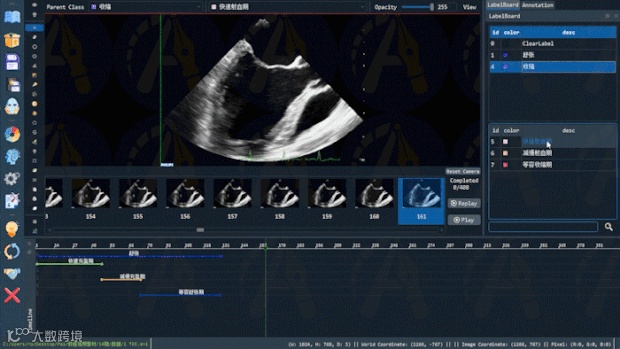

视频时间轴属性标注

医学视频影像通常由不同事件的影像片段沿时间轴构成,不同片段会具有不同属性的标注需求,如心脏在心动周期的不同动作、手术器械在手术不同阶段的动作类型等。目前鲜有标注软件提供对医学视频影像的时间轴标注功能。Pair提供的时间轴标注功能,通过便捷的交互设计,可快速对视频的任意片段进行多种属性的标注,高效推动视频标注工作的进展。具体说来,在时间轴标注功能下,鼠标右键拖动选中的标签到时间轴上对应的帧,即可完成对改视频片段的属性标注。Pair还提供时间轴跟随功能,方便用户观察片段所属的帧。若要修改标注,左键点击对应时间轴的端点进行拖动即可,操作方便。